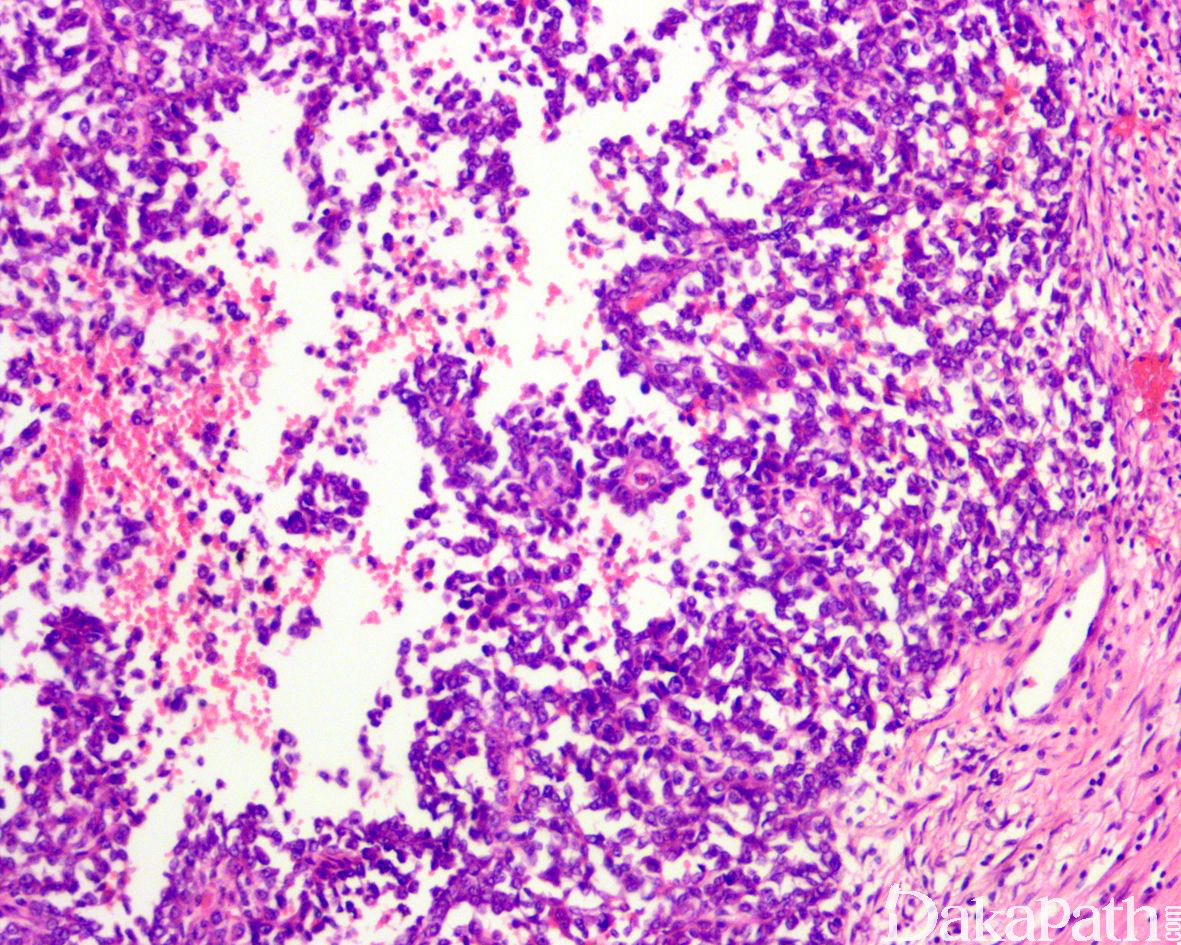

镜下,肿瘤呈片状和多结节状于肌层浸润,常见浆膜和粘膜累及;

肿瘤由弥漫一致的小圆至中等大上皮样细胞组成,胞浆弱嗜酸性,稀少至中等量,部分病例可见透明胞浆;其它常见的组织学构型包括假腺泡、假乳头、微囊、束状以及梁状结构;罕见的情况下可见顿挫的菊形团样结构,提示其神经外胚层分化的证据;

瘤细胞胞浆稀少,偶见丰富的嗜酸性胞浆,核浆比例高,核呈空泡状伴染色质边集,常见细小核仁;

核分裂象一般比较活跃(平均 6 个/10 高倍镜视野),常见不同程度的肿瘤性坏死;

MGNET 高度特征性的组织学表现为肿瘤内散在分布的破骨样巨细胞,与肿瘤细胞具有不同的核形态提示其反应性本质。破骨样巨细胞在不同肿瘤之间甚至同一肿瘤的不同区域之间分布具有明显的差异,有时候低倍镜下即可明显感知,有时需要更高倍数的视野仔细观察,有些病例可能完全缺如,特别是在活检标本中更是如此.